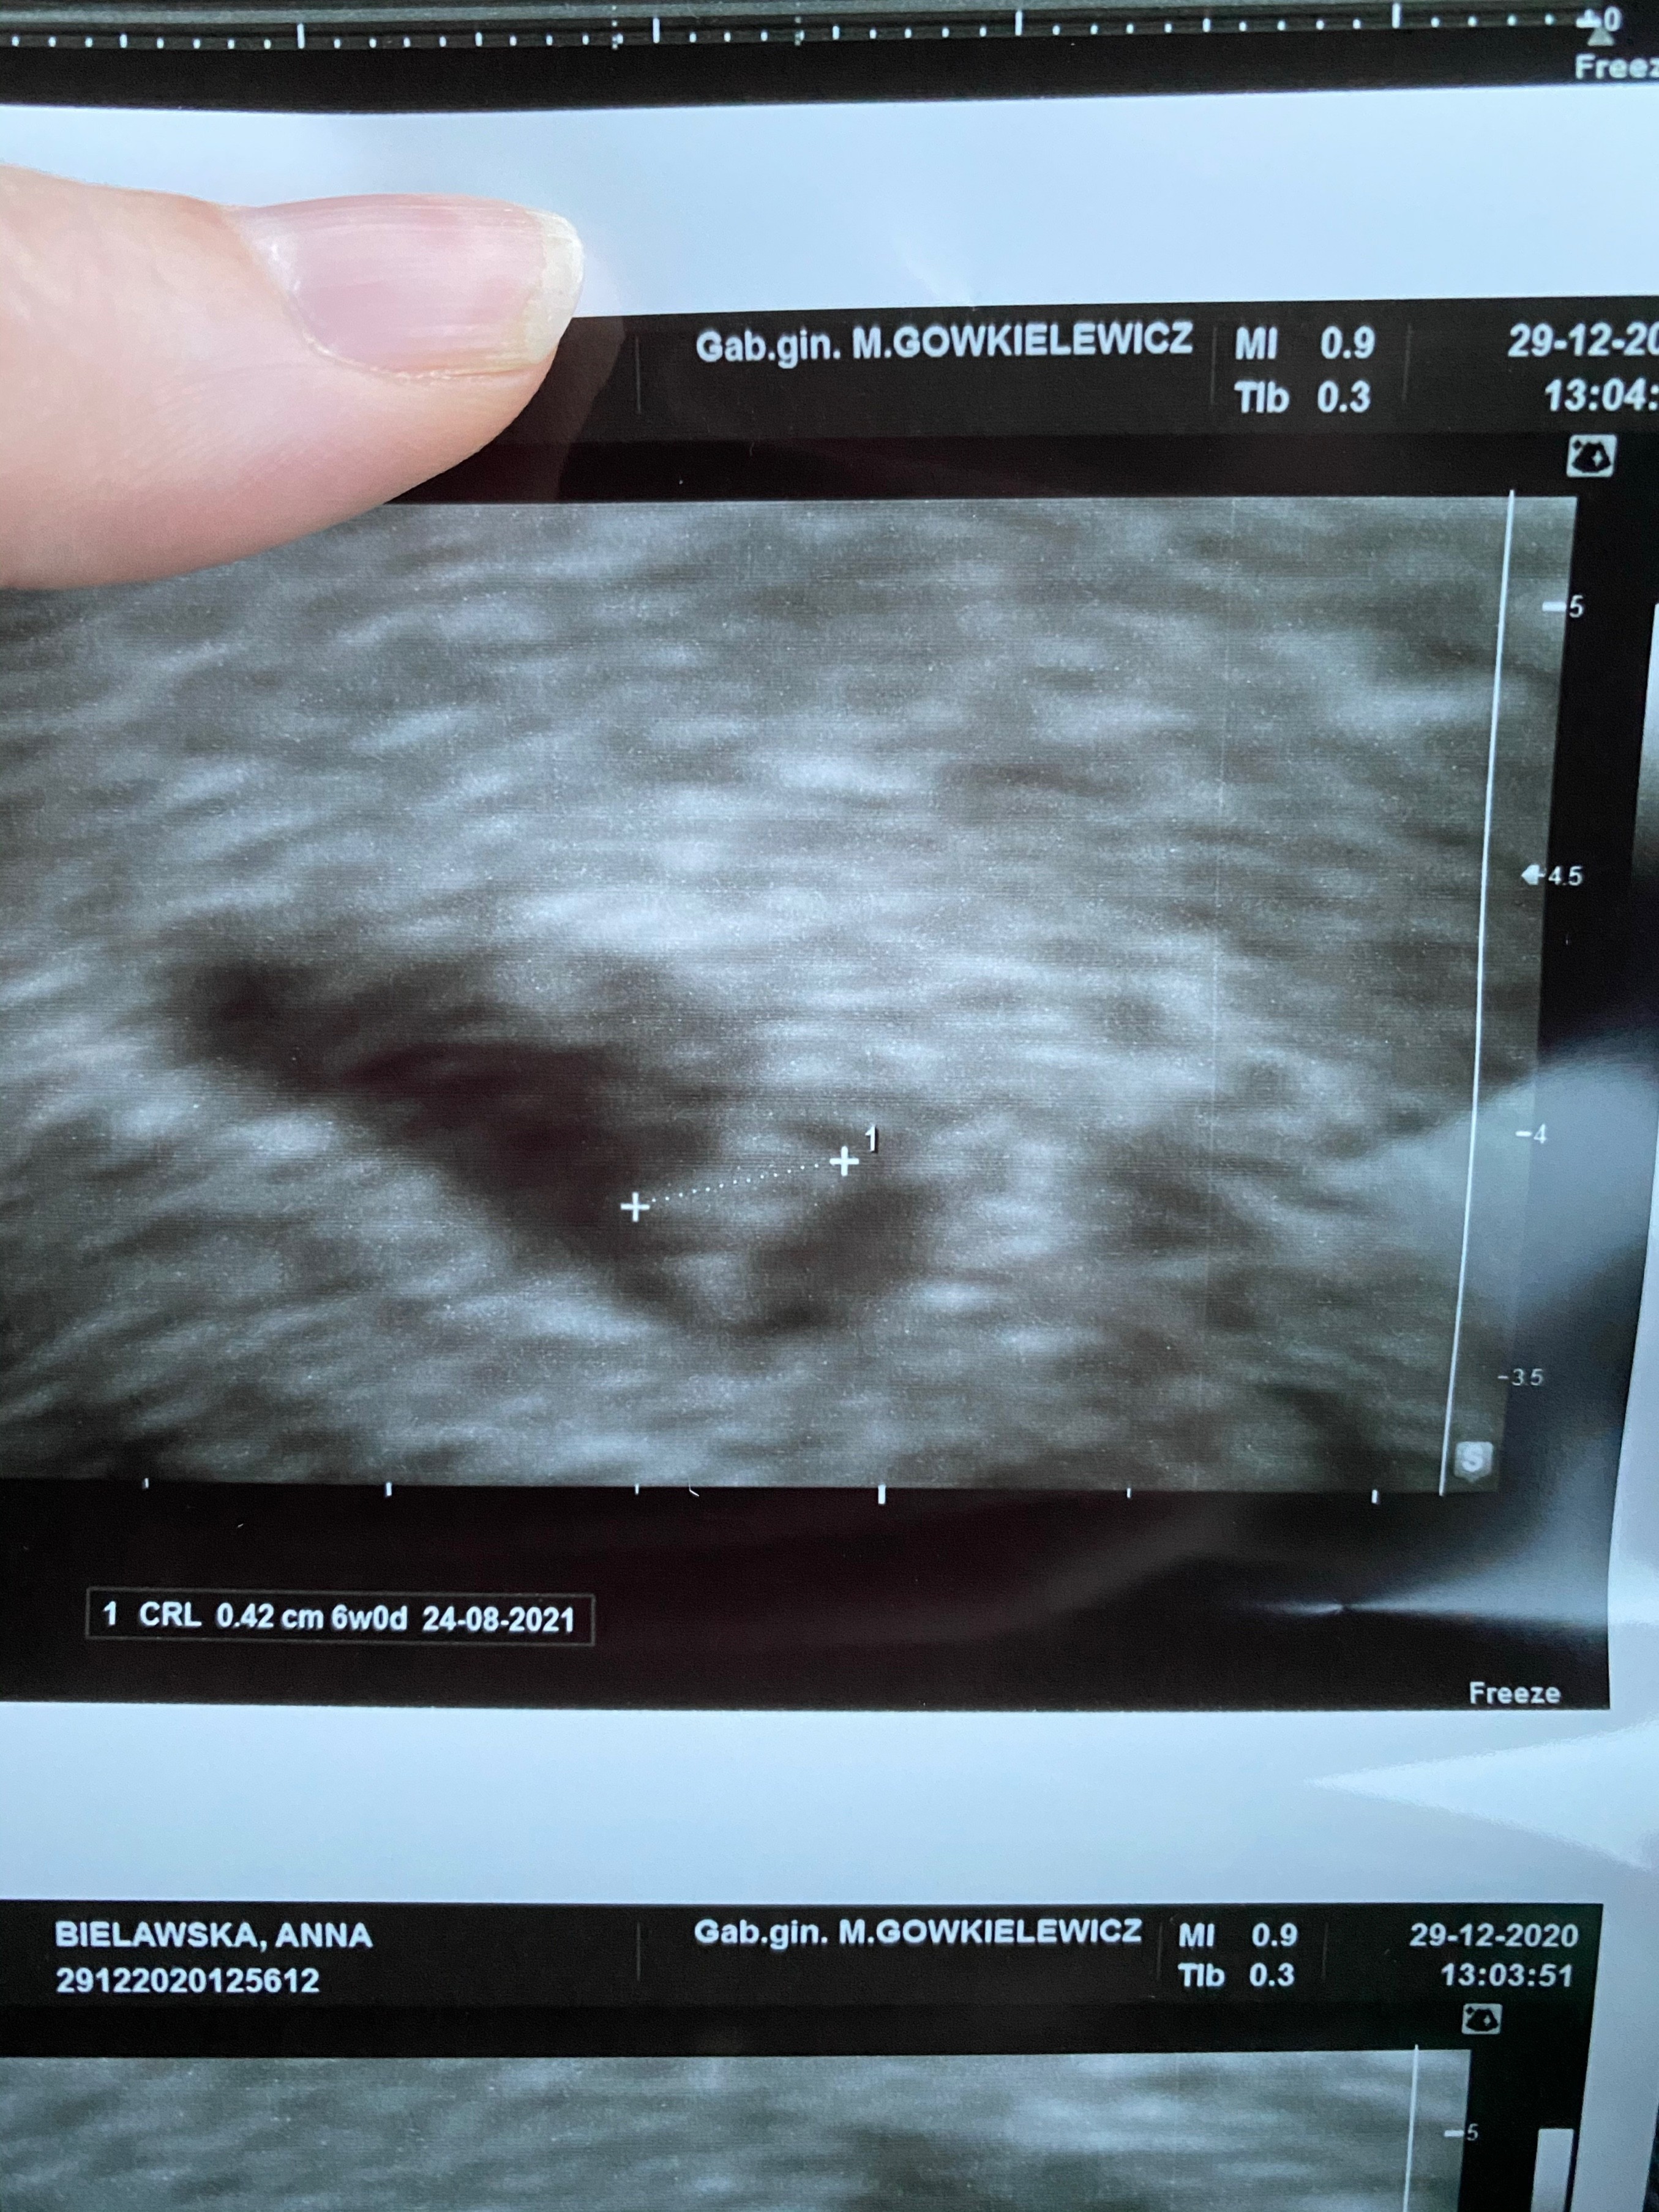

Wszystko dobrze. Maluszek tydzien młodszy ale serduszko pieknie bije. Widzialam jak caly pulsowal.

Termin z usg to 24.08. Odetchnelam z ulga. Zobacz załącznik 1220518